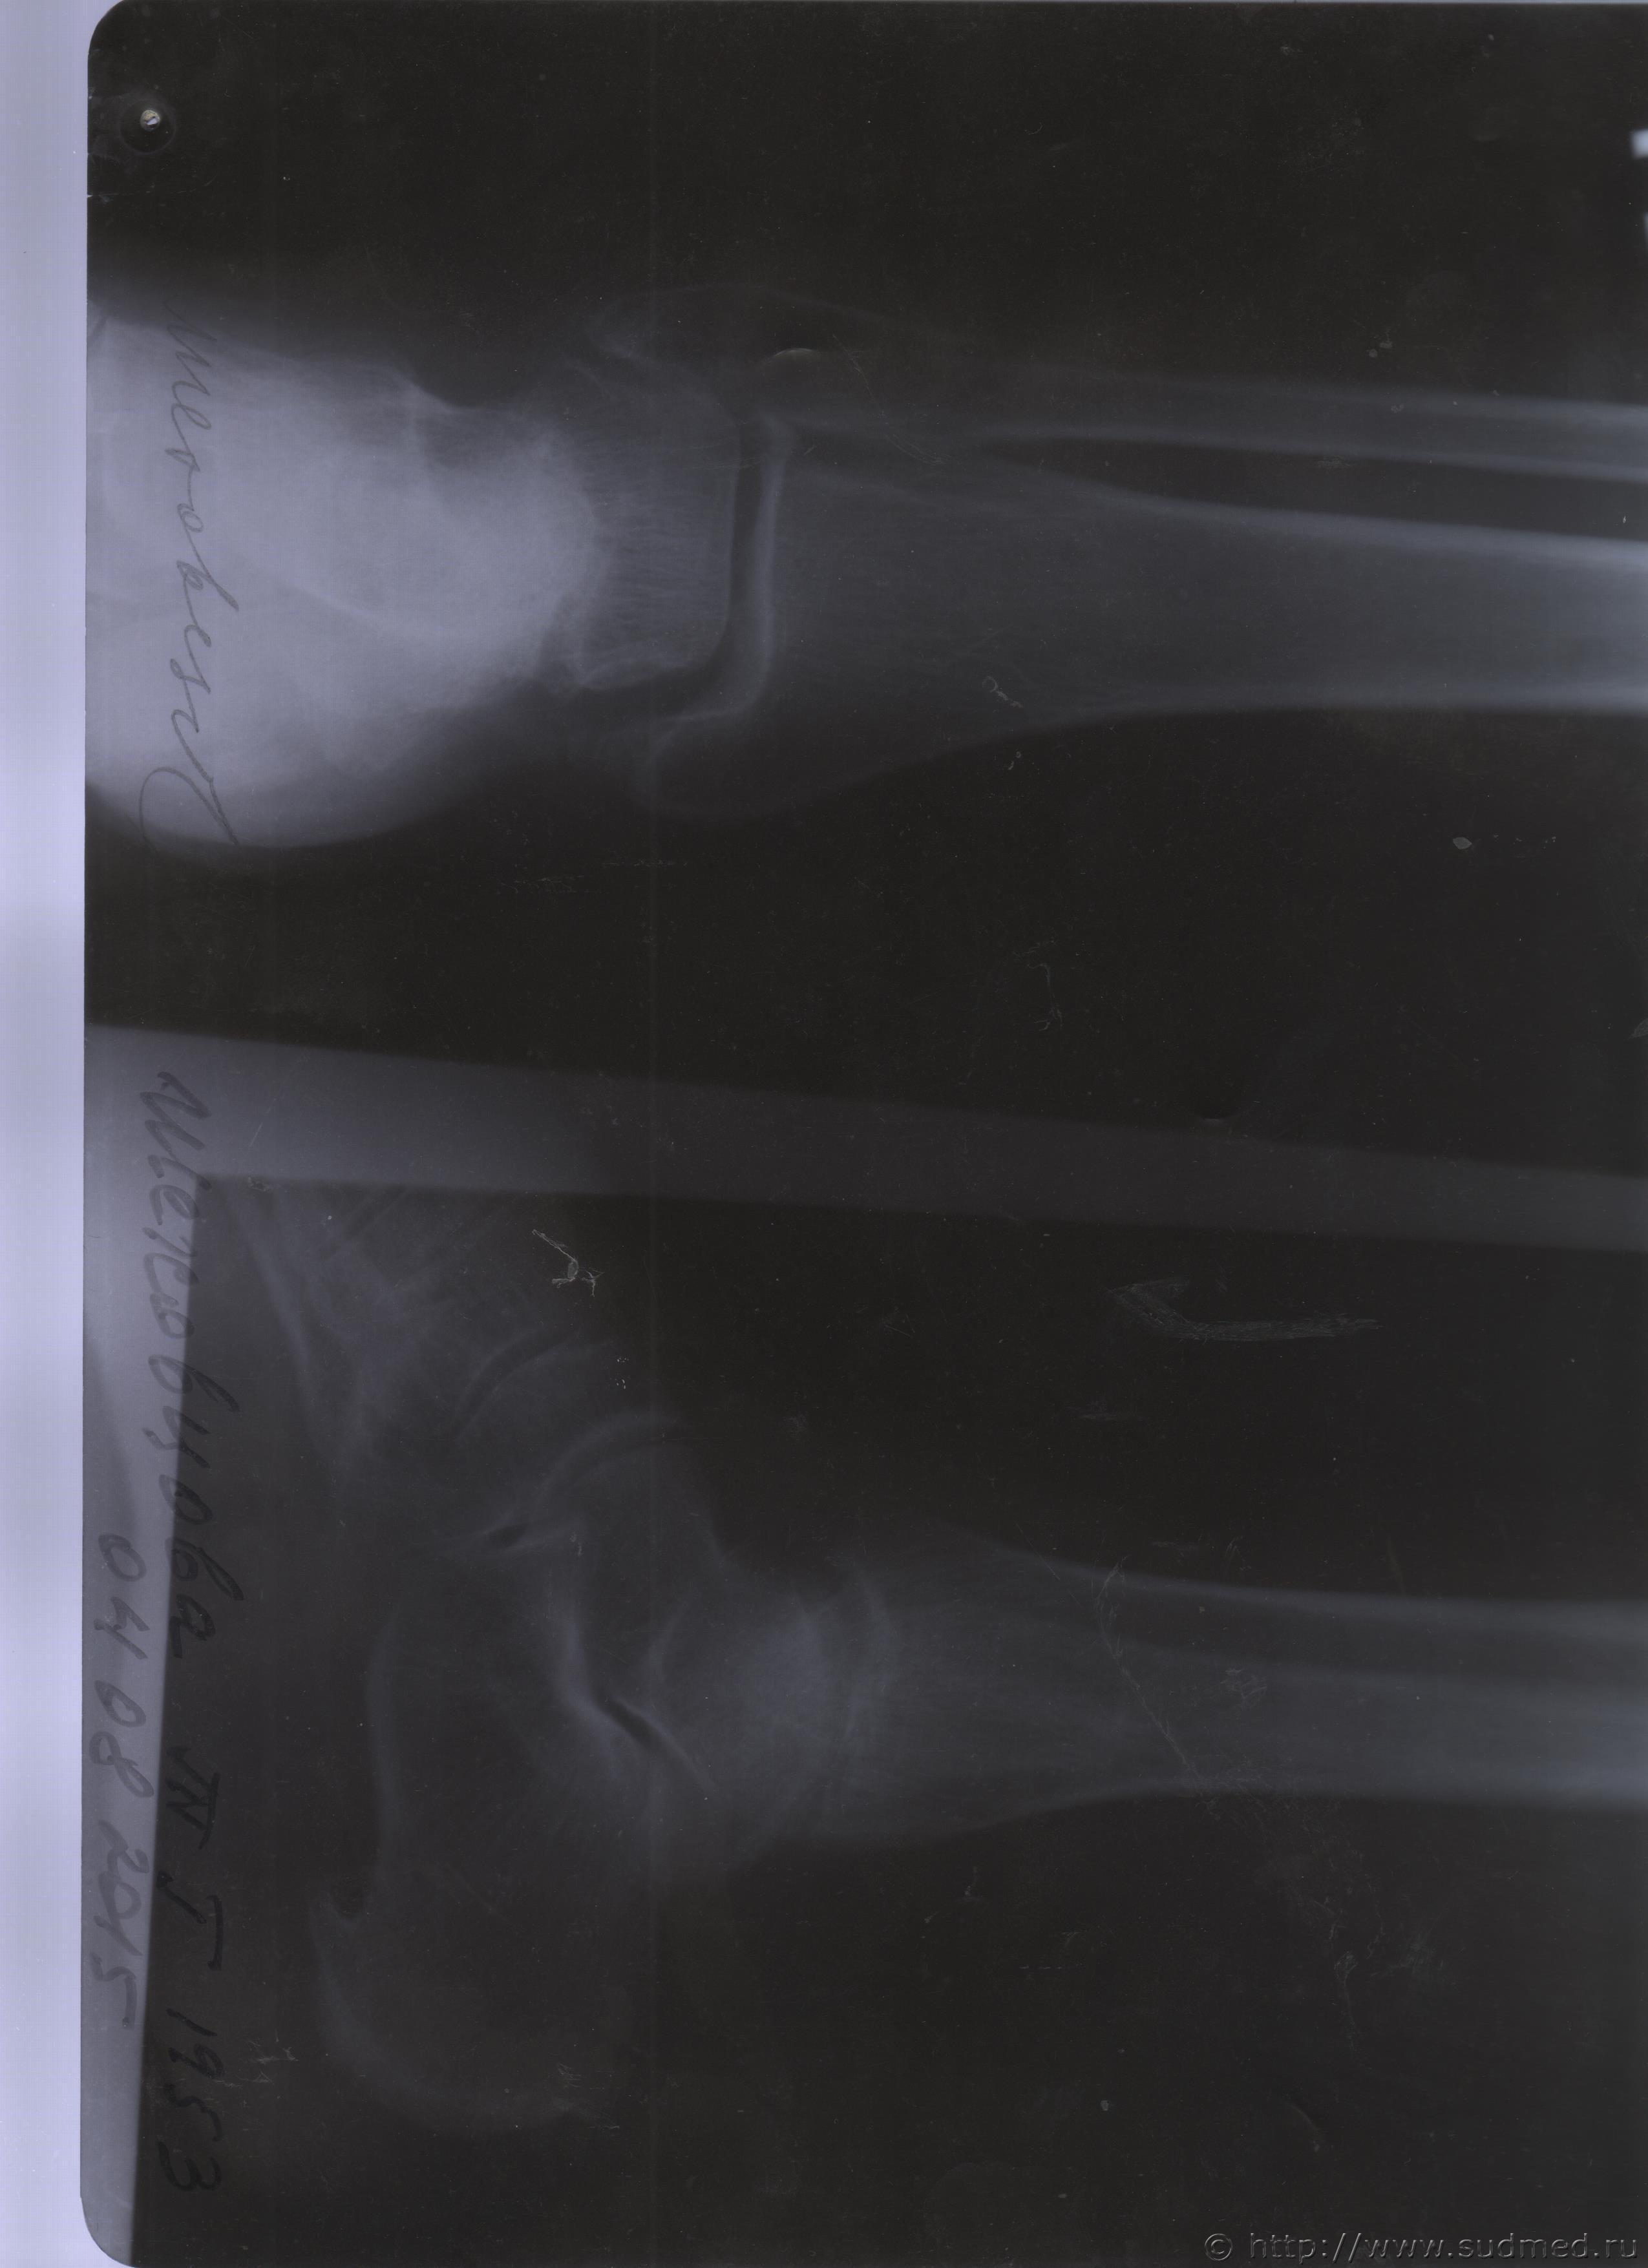

06.07.2015 г. при обращении в горбольницу мне выдали не описанный снимок( все рентгенологи были в отпуске) и справку № 4379 от 06.07.15 г. где диагноз: закрытый 2-х лодыжечный перелом правой голени без смещения. Копию справки прилагаю

За все 12 месяцев, что была на больничном, 8 раз делали снимки травмированной ноги и все заключения именно : «закрытый 2-х лодыжечный перелом правой голени без смещения».

После того, как был поставлен диагноз : «компрессионный перелом L2 позвонка поясничного отдела позвоночника». Амбулаторная мед карта, была украдена из кабинета врача травматолога. При восстановлении мед карты( в марте 2016 г.), врачом травматологом была взята копия справки от 06.07.15 г.из приемного отделения горбольницы. Справка № 4379 ( дубликат), диагноз : «закрытый 2-х лодыжечный перелом правой голени без смещения».

Посмотрите, это снимки за 12 месяцев.

Уважаемая Татьяна! По представленным Вами снимкам ничего сказать нельзя: нет маркировки даты каждого снимка (поэтому, невозможно их сравнивать друг с другом и соотносить с датой травмы), исследование непосредственно пленок гораздо более информативно, чем анализ представленных изображений (детали костной структуры в зоне перелома практически не видны).

Рекомендую проконсультировать все эти снимки у высококвалифицированного рентгенолога. Далее - по ситуации, т.е. в зависимости от его мнения. В любом случае, есть формальные основания для назначения дополнительной экспертизы, т.к., судя по представленному Вами фрагменту заключения эксперта, на экспертизу не были предоставлены все мед.документы с данными о лечении предъявляемой травмы (Вы пишете, что рентгенограммы делались на протяжении 12 месяцев, полагаю, что Вы и врачами наблюдались в течение этого срока, т.е. велась мед.карта).